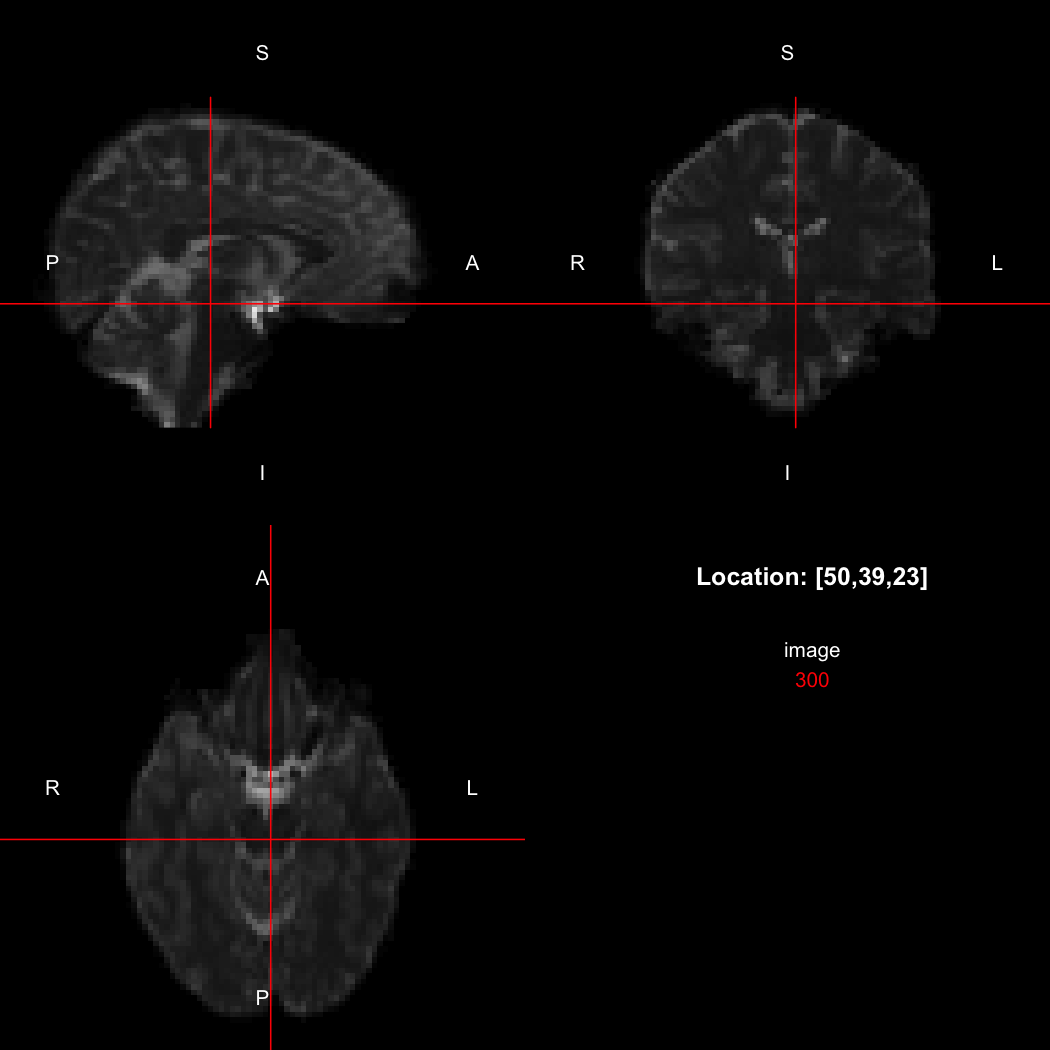

## [1] "LAS"So, here, “LAS” means that the positive x-axis points left, the positive y-axis anterior and the positive z-axis superior. This is the so-called “radiological” orientation convention, and can be requested when viewing images for those who are used to it:

view(image, radiological=TRUE)

Notice the left (L) and right (R) labels, relative to the view shown

above. Setting the radiologicalView option to

TRUE will make this the default for all future views.

image[50,39,23]

## [1] 300

orientation(image) <- "RAS"

xform(image)

## [,1] [,2] [,3] [,4]

## [1,] 2.5 0.0 0.0 -115.46610

## [2,] 0.0 2.5 0.0 -95.18523

## [3,] 0.0 0.0 2.5 -55.03814

## [4,] 0.0 0.0 0.0 1.00000

## attr(,"imagedim")

## [1] 96 96 60

## attr(,"code")

## [1] 2

## [1] 310

image[47,39,23]

## [1] 300Notice that the sign of the top-left element of the xform has now flipped, and the value of the image at location (50,39,23) has changed because the data has been reordered. The equivalent x-location is now 47, which is the 50th element counting in the other direction (96 - 50 + 1 = 47).